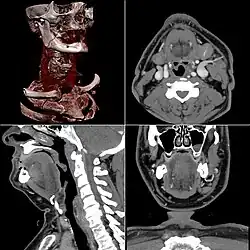

Многослойная компьютерная томография со внутривенным контрастным усилением и трёхмерной реконструкцией изображения

Многослойная («мультиспиральная», «мультисрезовая» компьютерная томография — МСКТ) была впервые представлена компанией Elscint Co. в 1992 году. Принципиальное отличие МСКТ от спиральных томографов предыдущих поколений в том, что по окружности гентри расположены не один, а два и более ряда детекторов. Для того, чтобы рентгеновское излучение могло одновременно приниматься детекторами, расположенными на разных рядах, была разработана новая — объёмная геометрическая форма пучка.